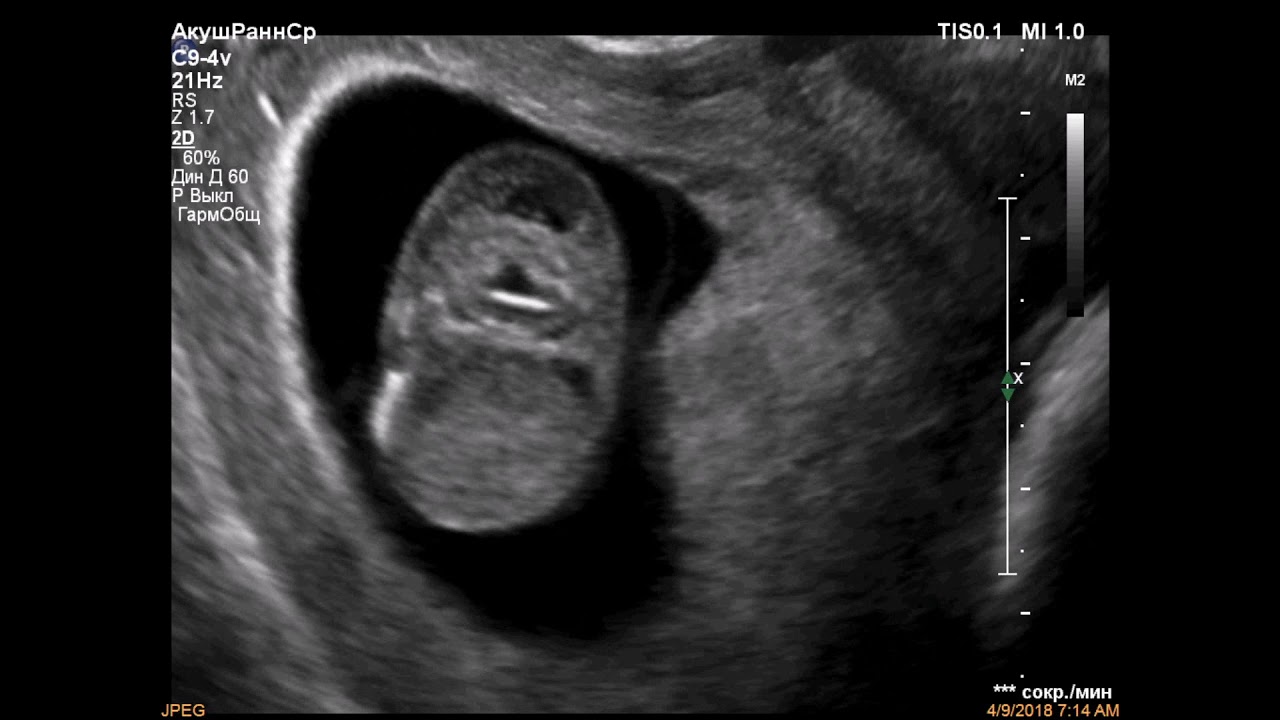

3. Измерения длины плода и области воротникового пространства

Во время обследования врач измеряет ребенка от макушки головы до крестца или до основания позвоночника. После того как длина этой части плода становится известной, приступают к исследованию шейной зоны – измеряют ее ширину. На мониторе аппарата УЗИ кожа выглядит белой полоской, а воротниковое пространство – черным полем.

ТВП определяется на ультразвуковом исследовании в 1 триместре

Затем измеряет наибольшую толщину скопления жидкости по задней поверхности шеи под кожей. Жидкость изображается на экране черным цветом, а кожа и мягкие ткани белыми. После проведенных измерений врач сравнивает полученный результат с нормативной таблицей.

Синим цветом на фотографии УЗИ выделено воротниковое пространство, толщина которого является важным параметром.

Воротниковое пространство — подкожное скопление жидкости в шее на затылке, отображающееся на УЗИ, как черная полоса. Оценка толщины воротникового пространства плода информативна только на сроке между 11 и 13 недель, при копчико-теменном размере 45-84 мм. После 13 недель скопление этой подкожной жидкости рассасывается.